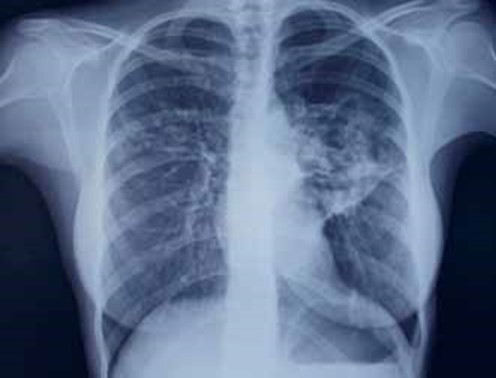

На обзорной РГ ОГК при поступлении 25.09.15 (рис. 2) справа за I–III ребрами и слева за II–IV ребрами – участки неоднородной инфильтрации легочной ткани размерами 3 × 6 см справа и 6 × 8 см – слева, при этом слева нельзя исключить очаги деструкции в центре инфильтрата. Корни уплотнены, расширены. Сердце и аорта не изменены. Заключение: двусторонняя верхнедолевая полисегментарная пневмония с элементами деструкции слева. (О.В. Фатенков с соавт., 2018)